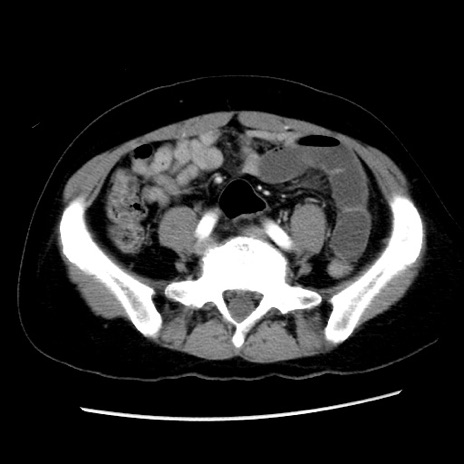

冠状断像

【症例】 50歳代女性

【主訴】 腹痛

【現病歴】前日生レバーを食べた。今朝に排便あり。 昼前に突然発症の腹痛を生じ、当院救急外来を受診した。

【既往歴】 子宮筋腫にてで子宮全摘後

【身体所見】 意識清明、腹部:平坦、軟、下腹部やや左を中心に圧痛・反跳痛あり、筋性防御あり

【データ】WBC 7800、CRP 0.07